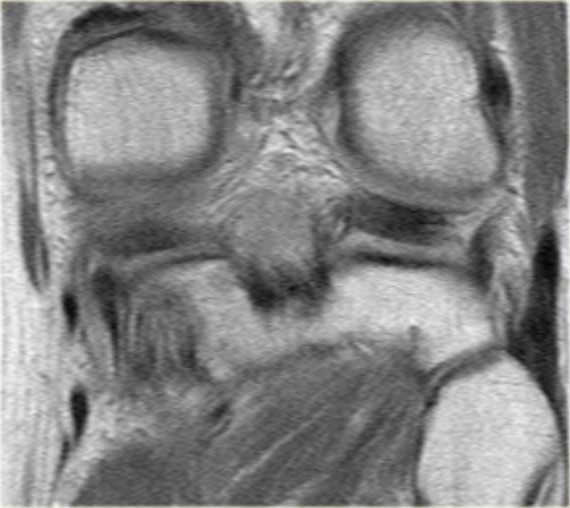

Bên trái là các hình ảnh PD sagittal của một trường hợp sụn chêm lật.

Toàn bộ sừng sau bị lật ra phía trước, tạo ra dấu hiệu sụn chêm rỗng (empty meniscus sign) (mũi tên).